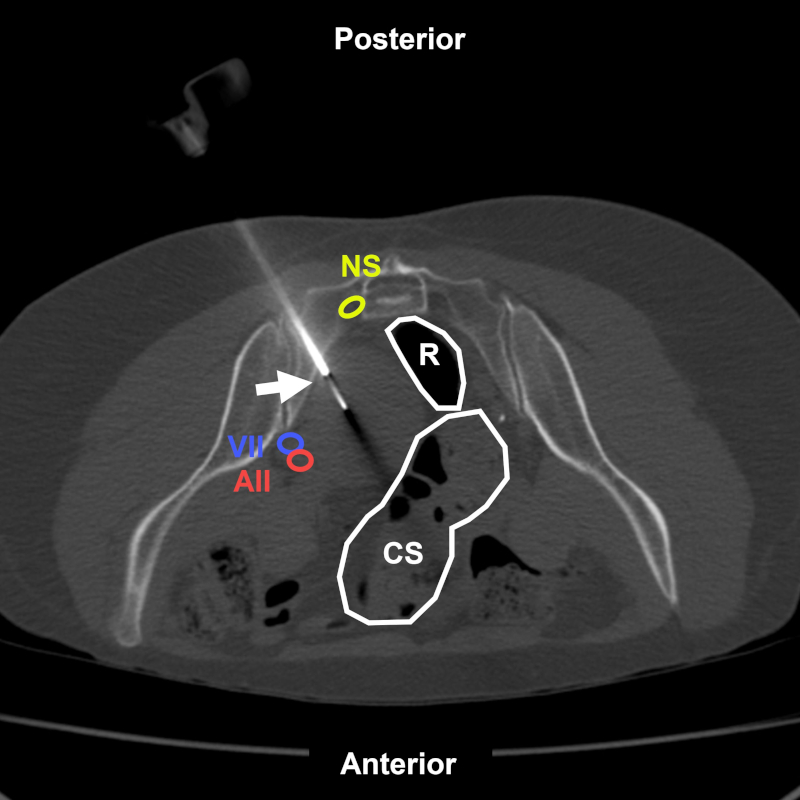

Figura 9

Varón de 73 años con antecedentes de cáncer pulmonar e imagen hipercaptante en la tomografía por emisión de positrones sin representación tomográfica ubicada en el hueso ilíaco izquierdo. BP coaxial transglútea (flecha) bajo TC. Estructuras a evitar: RN: raíz nerviosa de L5; AII: arteria ilíaca interna; VIC: vena ilíaca común. Aguja utilizada: Jamshidi 11 G con Franseen 18 G. Diagnóstico final: infiltración secundaria por tumor neuroendocrino.